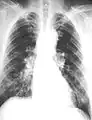

The abnormal chest x-ray and its interpretation remain the most important factors in establishing the presence of pulmonary fibrosis.[11] The findings usually appear as small, irregular parenchymal opacities, primarily in the lung bases. Using the ILO Classification system, "s", "t", and/or "u" opacities predominate. CT or high-resolution CT (HRCT) are more sensitive than plain radiography at detecting pulmonary fibrosis (as well as any underlying pleural changes). More than 50% of people affected with asbestosis develop plaques in the parietal pleura, the space between the chest wall and lungs. Once apparent, the radiographic findings in asbestosis may slowly progress or remain static, even in the absence of further asbestos exposure.[26] Rapid progression suggests an alternative diagnosis.

Asbestosis resembles many other diffuse interstitial lung diseases, including other pneumoconiosis. The differential diagnosis includes idiopathic pulmonary fibrosis (IPF), hypersensitivity pneumonitis, sarcoidosis, and others. The presence of pleural plaques may provide supportive evidence of causation by asbestos. Although lung biopsy is usually not necessary, the presence of asbestos bodies in association with pulmonary fibrosis establishes the diagnosis.[27] Conversely, interstitial pulmonary fibrosis in the absence of asbestos bodies is most likely not asbestosis.[11] Asbestos bodies in the absence of fibrosis indicate exposure, not disease.

Extensive fibrosis of pleura and lung parenchyma

Severe pleural fibrosis with focal calcification

61-year-old working industrially with asbestos for decades